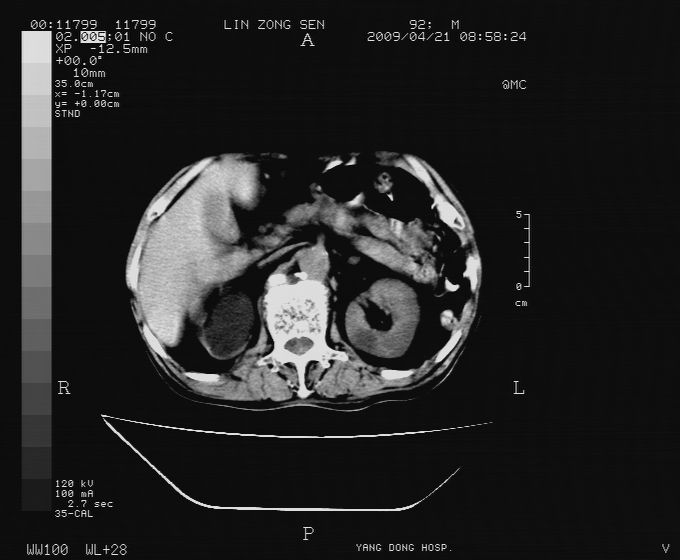

以下是引用卜一在2009-4-22 4:08:00的发言:[br]右肾积水伴输尿管上段积水!左侧肾多发囊肿!左侧腹壁软组织增厚,层次模糊,内密度较高—不排除血管瘤伴出血!